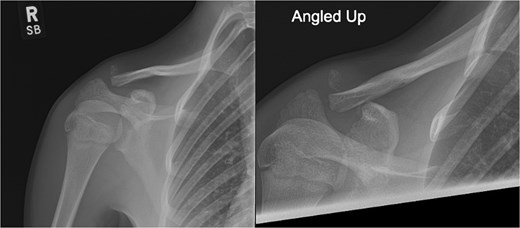

A 15-year-old male sustained a displaced Neer type IV lateral clavicle fracture during a rugby match, presenting with acute pain, deformity, and dorsal displacement without neurovascular compromise (Fig. 1). Imaging confirmed the diagnosis, and open reduction with TightRope and Fiber-wire reinforcement was performed. Early rehabilitation was initiated following short-term immobilization. At 6 weeks, the patient achieved pain-free shoulder function and radiographic stability. By four months, he regained full range of motion and returned to non-contact sports. Minor peri-scar numbness persisted, but imaging confirmed fracture union, and he was cleared for contact activities (Fig. 2A–B).

Radiographs of first case showing a displaced Neer type IV lateral clavicle fracture with deformity and displacement.